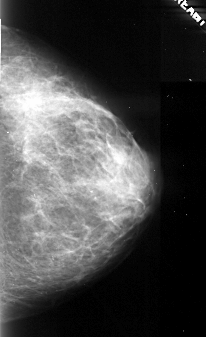

A_1105_1.RIGHT_MLO

RIGHT_MLO LINES 5266 PIXELS_PER_LINE 2611 BITS_PER_PIXEL 16 RESOLUTION 42 NON_OVERLAY